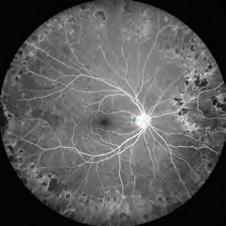

optomap®, the ONLY single-capture, 200° ultra-widefield retina image